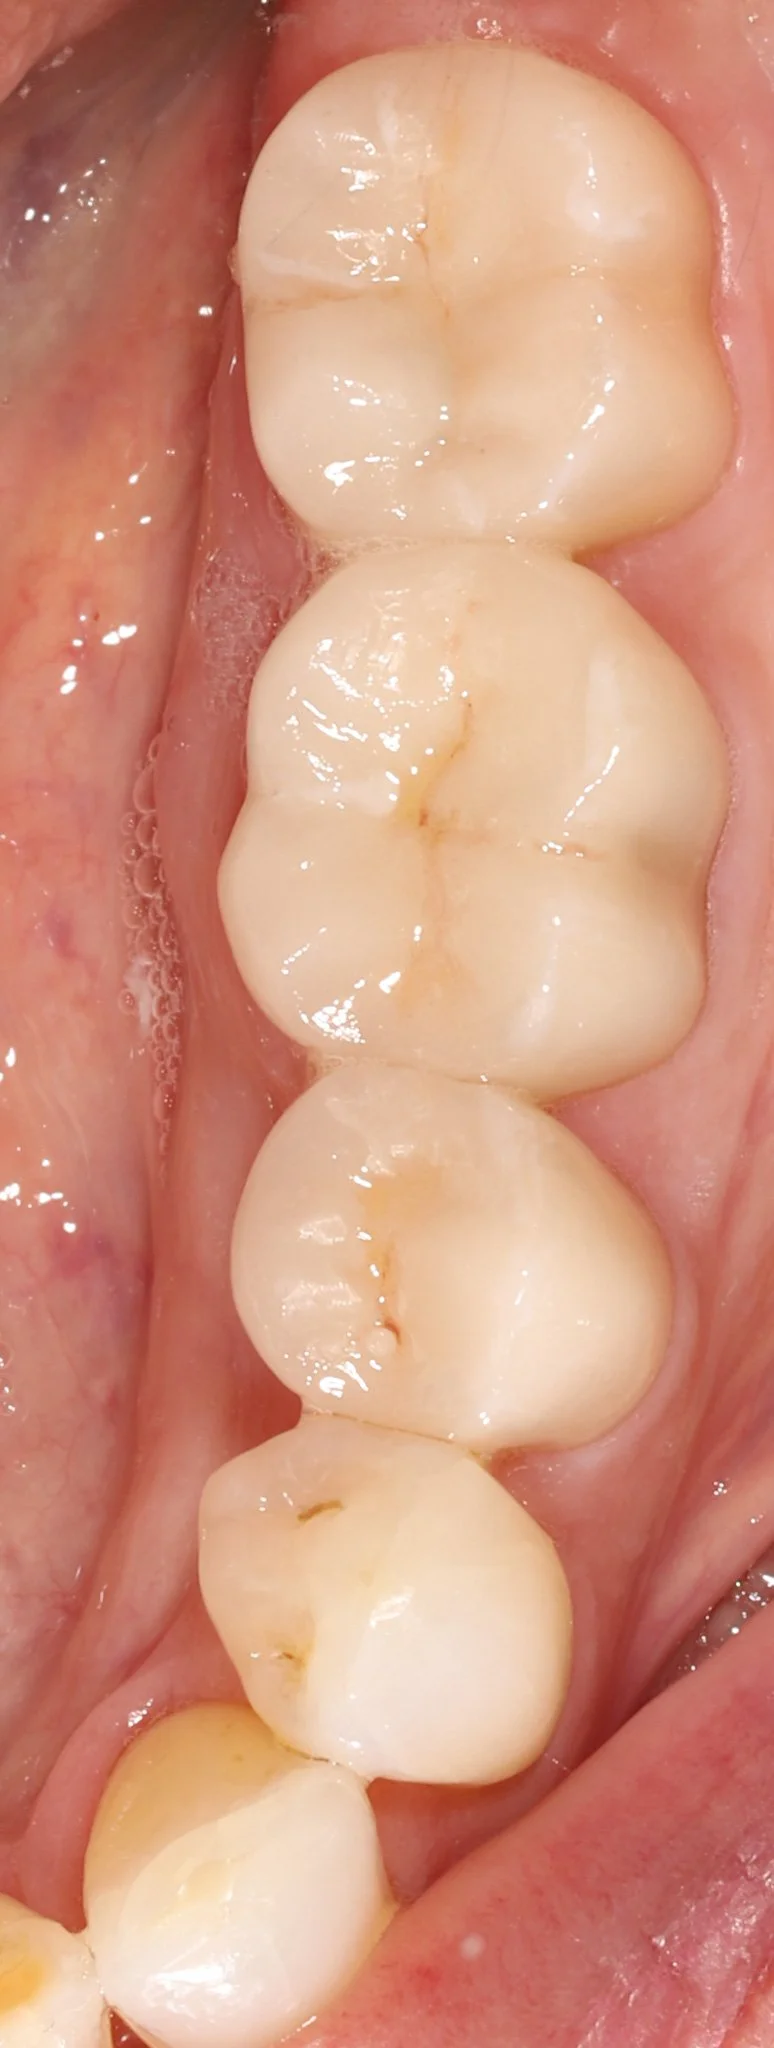

Close-up of molar teeth after restorations with bonded porcelain crowns showing optimal dental health.

After: New teeth blend seamlessly